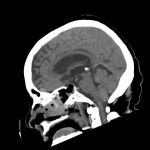

下垂体腫瘍

断層撮影

手術前1

手術後

No.’16_106 手術前1

No.’16_106 手術後